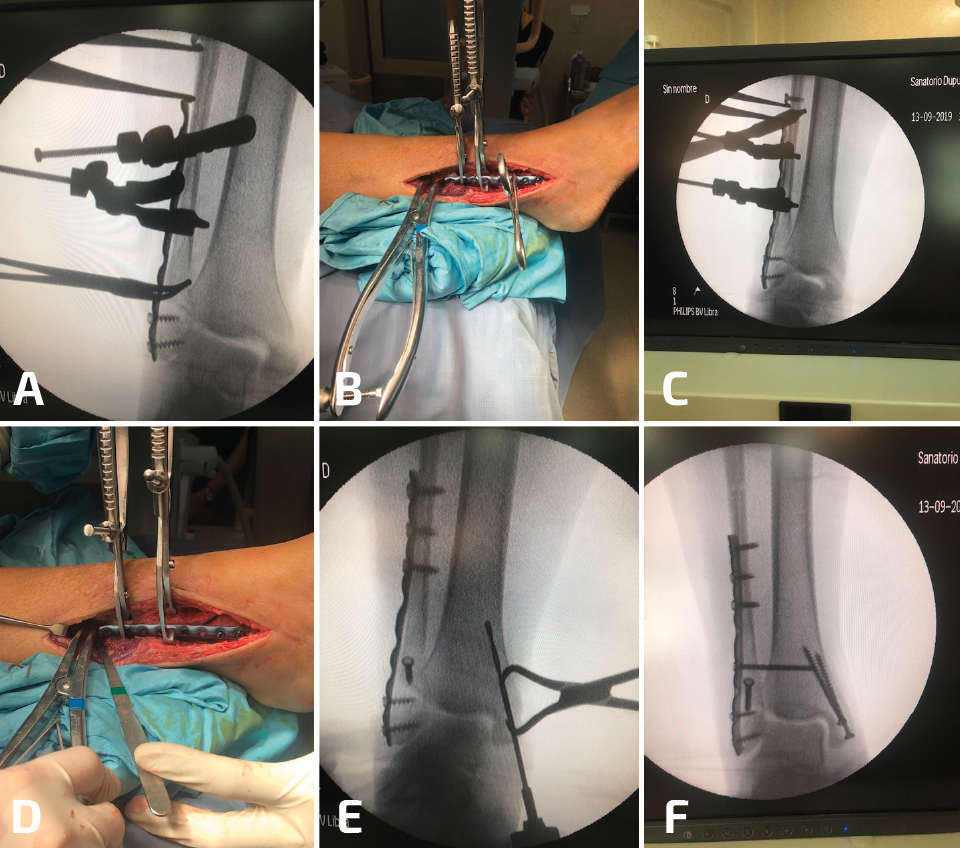

Durante la reconstrucción de la pseudoartrosis, es esencial realizar una artrotomía anterolateral para visualizar la reducción anatómica del peroné (Figura 1); sin embargo, el desbridamiento artroscópico de la articulación debe realizarse en forma simultánea no tanto para determinar el grado de artritis del tobillo, sino para tratar alguna lesión osteocondral no visible con la artrotomía anterolateral.

Figura 1. Cuando es necesaria una elongación significativa, se debe desbridar toda la sindesmosis anterior y dejar libre el peroné. Es indispensable para este paso un separador de láminas.

El tejido hipertrófico entre el maléolo interno y el astrágalo debe resecarse desde el receso interno para el correcto reposicionamiento del astrágalo. Esto se puede lograr por vía artroscópica o mediante una artrotomía anteromedial. Esto es importante tenerlo en cuenta, ya que una pequeña cantidad de tejido en la gotera interna puede bloquear el correcto desplazamiento medial del astrágalo dentro de la mortaja. La pseudoartrosis del peroné por lo general se asocia con un desplazamiento lateral del astrágalo, con un aumento del espacio claro medial, motivo por el cual se debe limpiar toda la gotera interna (Figura 2).

Figura 2. Aquí mostramos la técnica de elongación. Después del desbridamiento de la sindesmosis, se coloca la placa sobre el peroné y de colocan 2 o 3 tornillos distales (A, B). Se coloca un tornillo de 3,5 en el peroné proximal a la placa y el separador de láminas entre el tornillo y el borde proximal de la placa (C, D). En este caso, para corregir la consolidación viciosa del maléolo medial, se realizó una osteotomía (E) y el control de radioscopia intraoperatorio muestra una buena reducción de la sindesmosis (F).